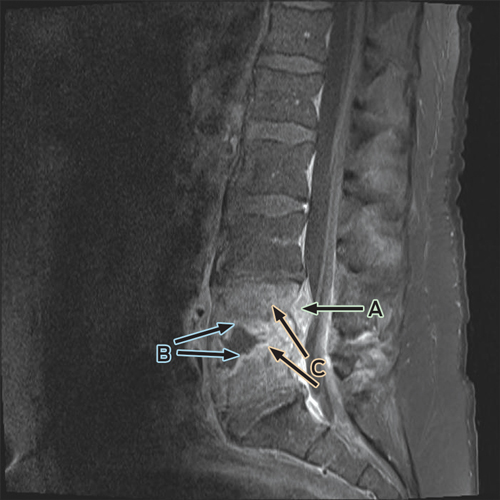

Despite ongoing cephazolin therapy, the patient developed increasing pain over the right sternoclavicular joint. Computed tomography imaging demonstrated changes consistent with a joint effusion, localised oedema, septic arthritis and osteomyelitis of the upper manubrium and medial right clavicle (Box 2). After initial conservative management without symptom resolution, surgical debridement was performed, and culture of the excised tissue grew MDR E. coli. The patient subsequently complained of lumbar back pain, and MRI of the lumbar spine showed changes consistent with an epidural abscess together with immediately adjacent discitis and osteomyelitis at the L4–5 vertebrae (Box 3). An orthopaedic consultation recommended conservative management, and the patient’s primary care was transferred to infectious diseases physicians. After 5 weeks of intravenous cephazolin therapy in hospital, he was discharged with a treatment regimen of intravenous ceftriaxone 2 g daily delivered by an elastomeric infusion device (Baxter) managed by the home-based acute care service.